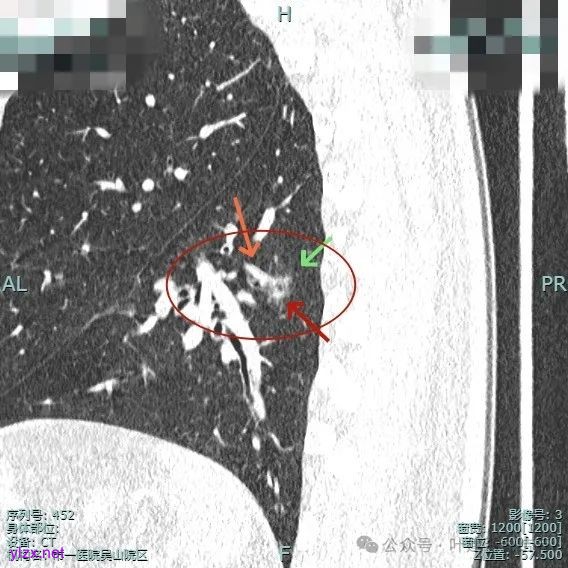

主病灶位于下叶后基底段下肺静脉水平,次病灶在同一层面位靠外基底段交界附近。

薄层上看主病灶不纯,有实性成分,也有血管穿行;次病灶是纯磨,微小的结节,但轮廓与边界较为清楚。

主病灶有血管进展与异常增粗,灶内有实性成分,中间有小空泡征。

进入病灶内的血管壁毛糙不平,有异常增粗。

血管进入且异常增粗,其余部分密度为磨玻璃及少许点状偏高成分。

主病灶混合密度,血管进入;次病灶小且淡,但轮廓清。